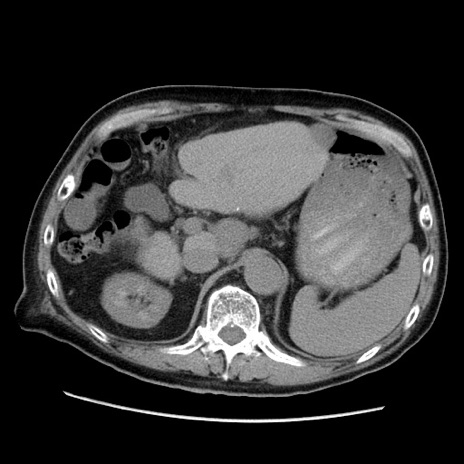

症例21(横断像)

【症例】70歳代男性

【主訴】腹痛

【現病歴】肝硬変・肝細胞癌にてかかりつけの方。約9時間前に食後より腹痛出現。症状が徐々に増悪し、嘔吐出現したため来院。

【既往歴】肝硬変、肝細胞癌(RFA、TACE後)

【身体所見】意識清明、表情苦悶様、BT 36℃、BP 129/78mmHg、P 88bpm、SpO2 97%(RA)、右上腹部から心窩部にかけて圧痛あり、反跳痛なし、筋性防御あり。

【データ】WBC 5800、CRP 0.16